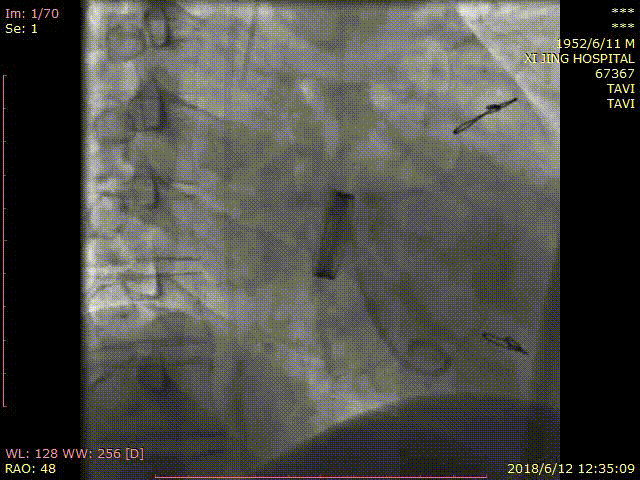

术中DSA影像:

手术过程